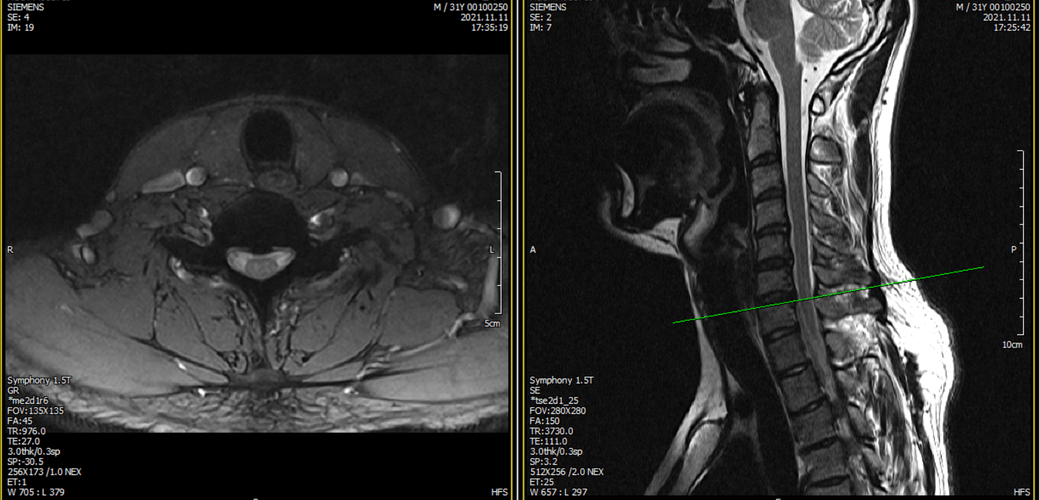

아래는 저의 경추과 요추 MRI 사진 첨부합니다.

• 1번 째 사진

• 2번 째 사진

• 3번 째 사진

• 4번 째 사진